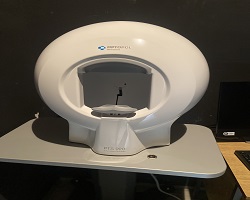

У Општу болницу Панчево ускоро стижу нови апарати, у вредности од 6о милиона динара, захваљући новцу који је обезбедио Покрајински секретаријат за здравство. Централни мониторинг за Службу неурологије, холтер систем за Службу кардиологије, ултразвучни апарат за Службу радиологије као и нови софтер за чување података. УПС систем за скенер који ће чувати скенер од прекида дотока струје. Набавићемо нову централну остеодензитрометрију за дијагностиковање остеопорозе. Ови и многи други апарати помоћиће у лакшем дијагностиковању болести и квалитетнијем лечењу. |

Захваљујући јавном конкурсу Покрајинског секретаријата за здравство за доделу средстава за изградњу, одржавање и опремање здравствених установа чији је оснивач Аутономна покрајина Војводина, Општа болница Панчево добила је прилику да набави два високорезолуциона 12-канална ЕКГ апарата са припадајућим системима и опремом. |

Општа болница Панчево може се, са изузетним поносом, похвалити да је набавила значајну медицинску опрему за одсек гастроентерологије са ендоскопском дијагностиком. Ова изузетно вредна набавка реализована је из средстава која су нашој болници додељена након спроведеног јавног конкурса Покрајинског секретаријата за здравство за доделу средстава за изградњу, одржавање и опремање здравствених установа чији је оснивач Аутономна покрајина Војводина. |